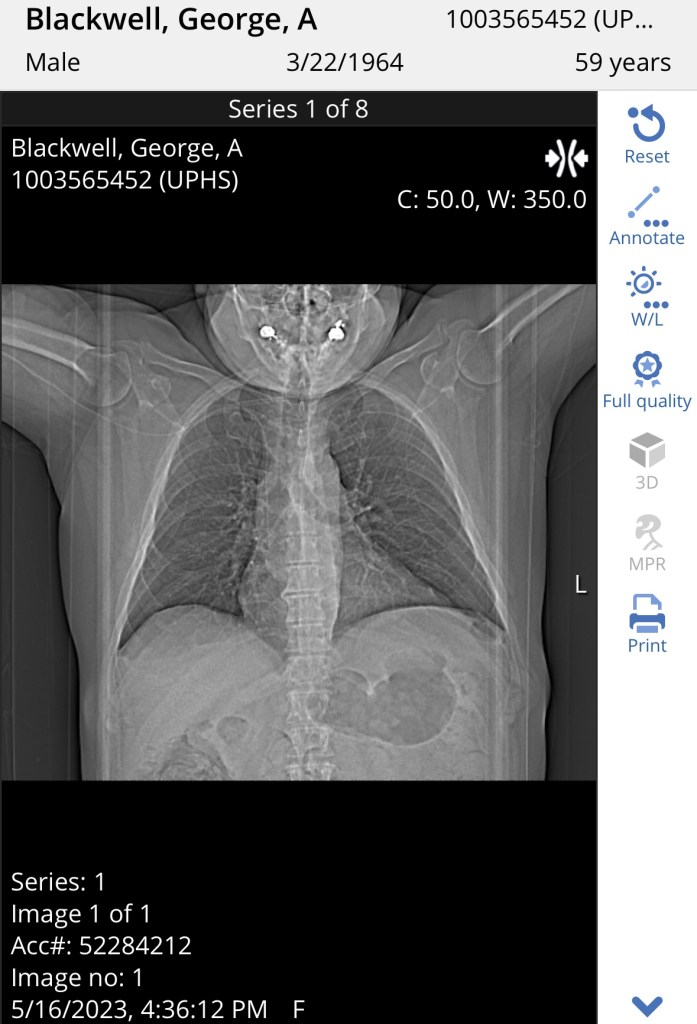

Yesterday was a busy and informative day. George had his hospital discharge visit with his pulmonologist, Dr. Heyman. She had him take a pulmonary function test (PFT) when we first arrived. Then we were taken back to a consult room to meet with her and go over the results of that test and the CT scan he received the week before.

The CT scan showed good improvement from the last one he had while hospitalized. Good news! The doctor said that means the choice to treat with steroids was correct. So, it’s time to taper down the Prednisone dosage more, in a conservative and slow manner, which means he will be on steroids until mid-July. That will most likely delay George’s transplant because Dr. Heyman said Dr. Loren will most likely not want to do the transplant while he’s still on steroids. So, she will consult with her and then we will plan for the next few months.

She also said she strongly suspects that George did NOT have drug induced lung injury, but that he had post-COVID organizing pneumonia. You can read about it here…https://www.ncbi.nlm.nih.gov/pmc/articles/PMC9780828/. She made this decision based on the timing of the appearance of the horrid cough he had and how it has responded to steroids, rather than antibiotics or other treatments.

He did well on his PFT, but of course not as well as the one he took last year to clear him for his first transplant. His lungs have been through A LOT! He will need to get clearance for his lungs to undergo the chemo regimen for the second transplant. I’m not sure where he stands now, but Dr. Heyman encouraged him to get out and walk/exercise his lungs. He has been doing well, walking 2 – 2/12 miles when he gets time to get out to the track. He has to be careful of sun exposure so he likes to go in the early evening. He will go back to visit Dr. Heyman in July when his steroid taper is complete, provided no issues arise during the taper.